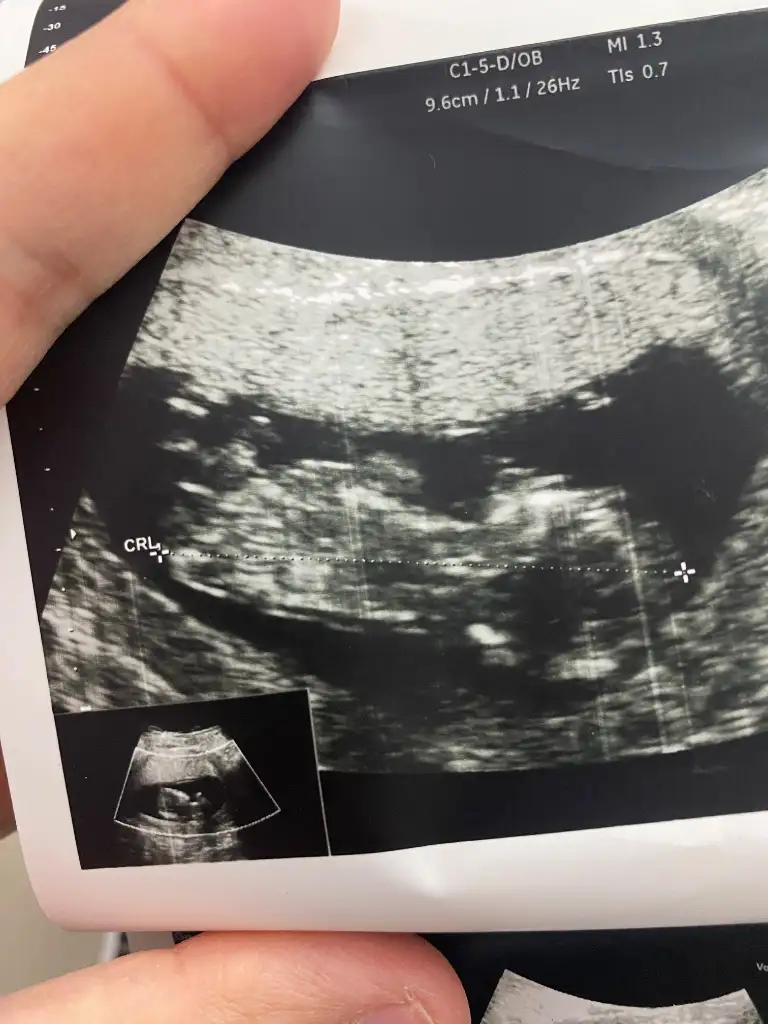

Sizce benimki neyNub teorisine göre kız![]()

Nub çıkıntısını göremedim. Başka resim var mı?Sizce benimki ney![]()

Nub a göre kız canımMerhaba, 13.hafta ultrason görüntüsüne göre cinsiyet tahmini yapabilir misiniz